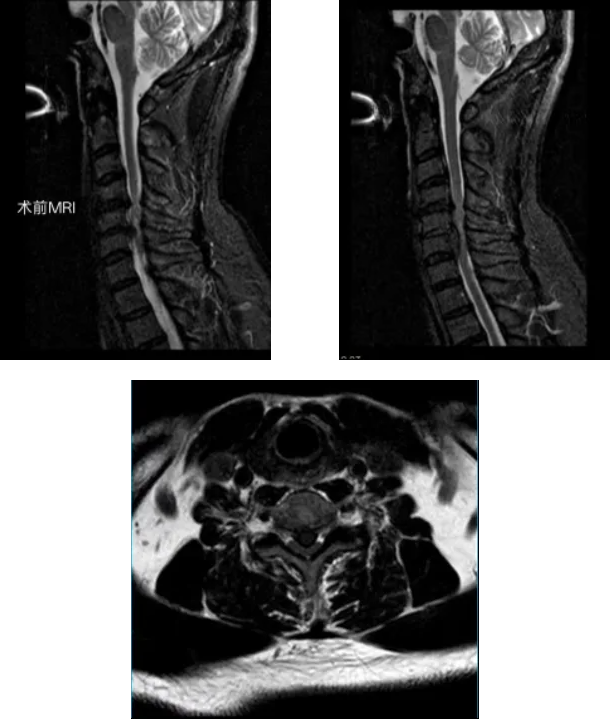

经详细问诊与影像检查,李永革主任很快锁定了“元凶”:颈椎MRI显示,徐先生的颈4/5、颈5/6、颈6/7椎间盘突出,其中颈5椎间盘已脱出,严重压迫脊髓,确诊为脊髓型颈椎病。

面对徐先生明确的脊髓压迫和神经损伤,必须尽快手术减压。李永革主任团队经周密评估,为患者量身定制了方案:采用 UBE(单侧双通道内镜)技术施行颈前路微创减压融合术。